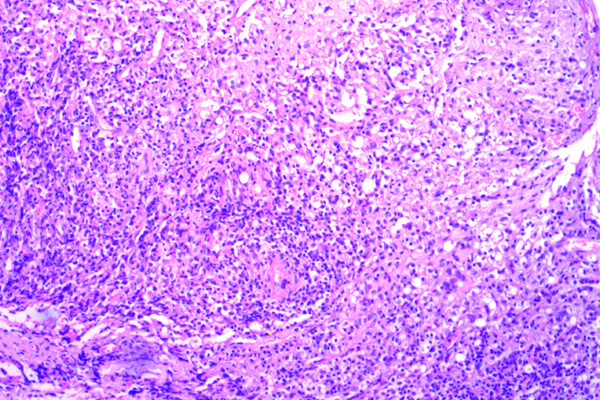

Se aprecian cambios cónsonos con una dermatitis granulomatosa crónica con ulceración.

Este infiltrado es típicamente granulomatoso e incluye, macrófagos, células gigantes multinucleadas de tipo Langhans y de tipo cuerpo extraño, formadas por la fusión de macrófagos, así como linfocitos y células plasmáticas, especialmente en la periferia de los granulomas.

La característica más notable es un infiltrado inflamatorio denso y difuso que ocupa la dermis.

El infiltrado inflamatorio es intenso, a menudo respetando un «espacio» debajo de la epidermis (la zona de Grenz). Sin embargo, como en este caso puede estar ausente por la extensa ulceración.

Destaca la presencia de células gigantes multinucleadas de tipo Langhans y de tipo cuerpo extraño.